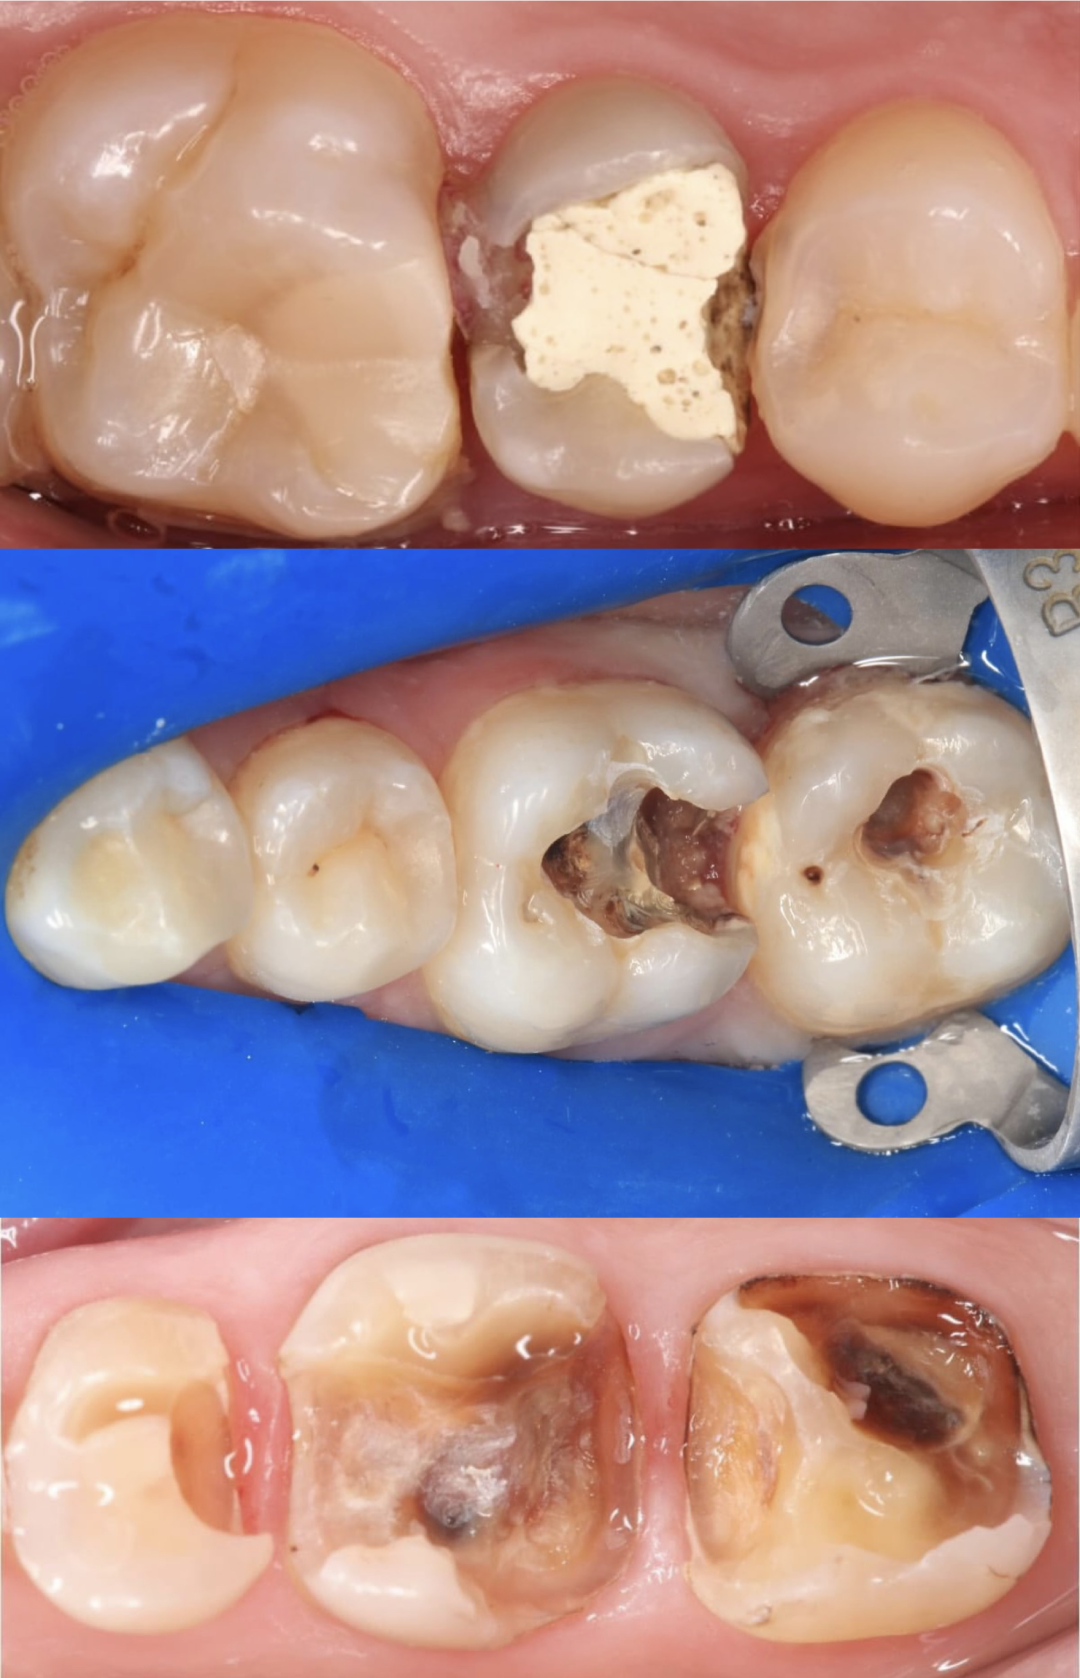

术前照片

主诉:右下后牙充填物脱落3天。

现病史:患者自诉右下后牙五年前在外院充填,3天前充填物脱落,否认自觉症状,由于食物嵌塞,影响进食,遂来我院就诊。

既往史:体健。

口腔检查:46远中邻面可见深大龋洞,窝洞内可见黑褐色腐质,质软,至牙本质深层。冷诊无明显反应。叩痛(-),牙髓活力测试正常。

辅助检查:46根尖未见异常。

诊断:46深龋

治疗方案:46嵌体修复

局部麻醉下进行去除腐质,可见远中邻面边缘位于龈下。由于近髓,剩余核心区域腐质橡皮障隔离后再进行去除。

橡皮障隔离患牙,去净腐质,然后进行详细的生物力学分析,远中舌尖无牙本质支撑,需要牙尖覆盖,降低1.5mm左右,远中颊尖厚度足够。近中邻面边缘嵴完整,远中邻面边缘需要进行CMR。